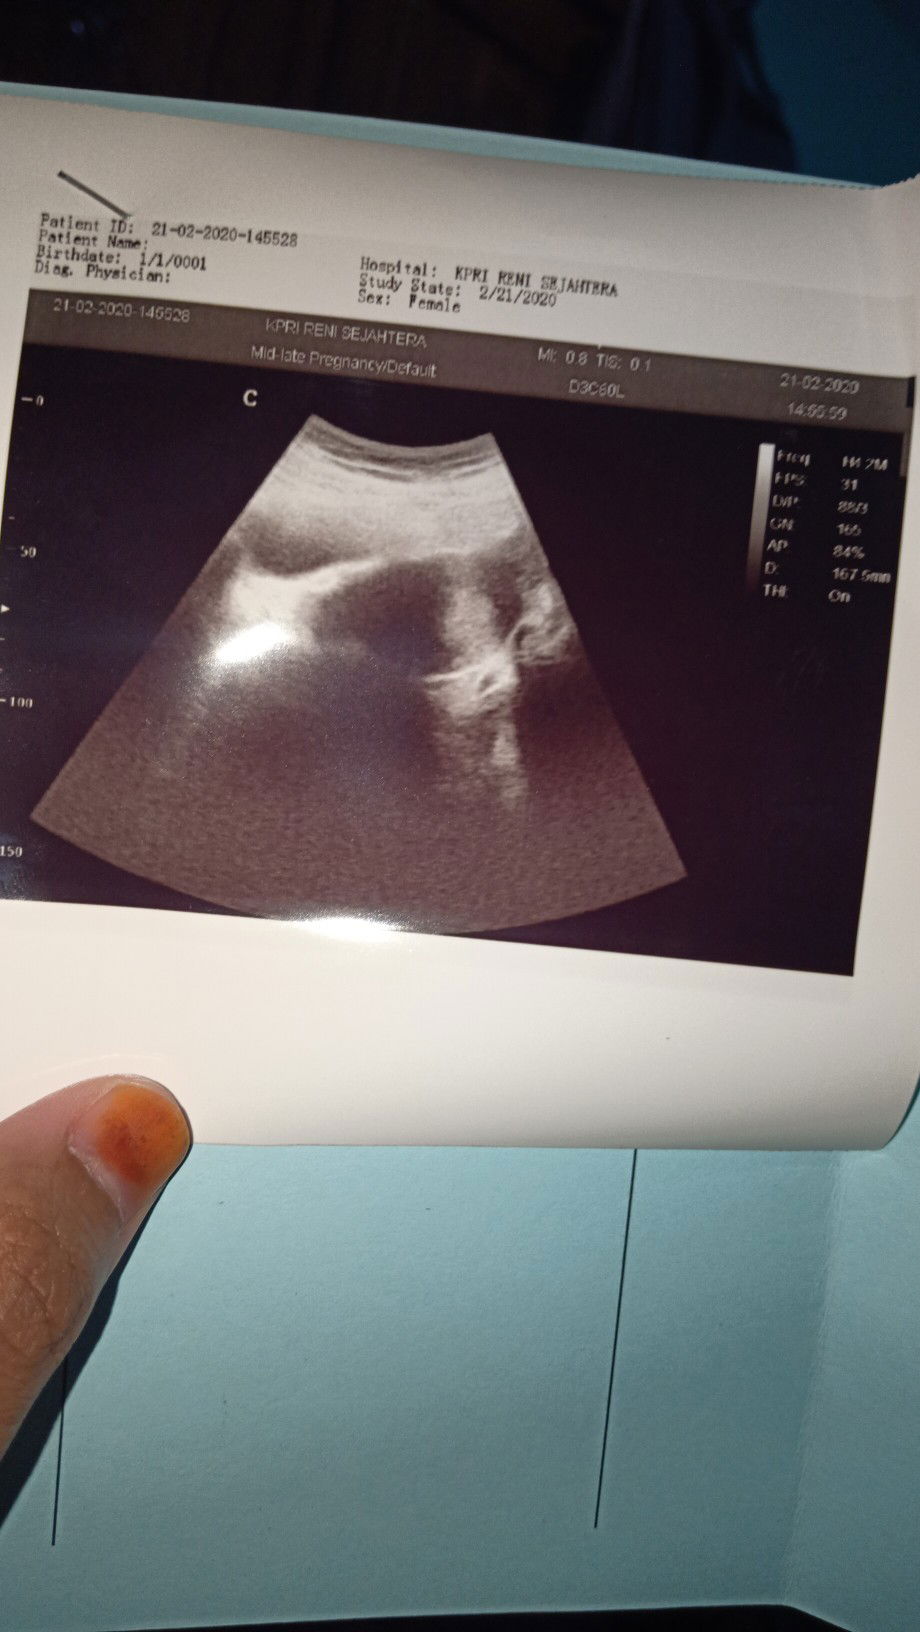

Di USG hasil nya seperti ini Tapi saya sudah telat seminggu dari masa haidh bulan lalu yang harusnya bulan ini tanggal 15 haidh. Di coba testpeck masih garis satu, tapi di aplikasi ini bayi nya katanya udah masuk 5weeks??? YaAllah bunda bunda